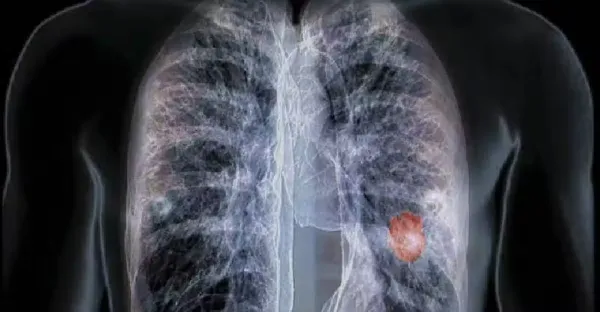

不抽菸不喝酒!45歲女確診「晚期肺癌」只因長期在做兩件事 5類高危人群要重視「早期癥狀」

全球一年1929萬人患癌!四大惡性腫瘤「一發現即晚期」 再次提醒:這4種食物「再愛吃也要忌口 」